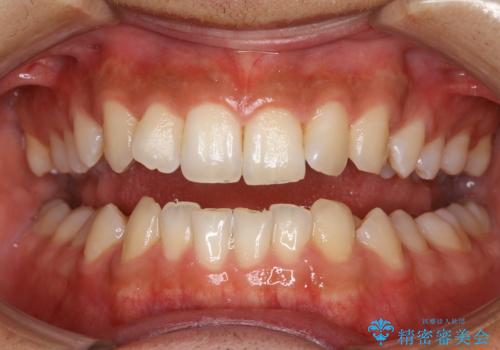

- 歯を白くしたいとのことでした。

オフィスホワイトニング(TION Whitening・処置前クリーニング込み)コースを行いました。

処置後は艶のある綺麗な白さになりました。